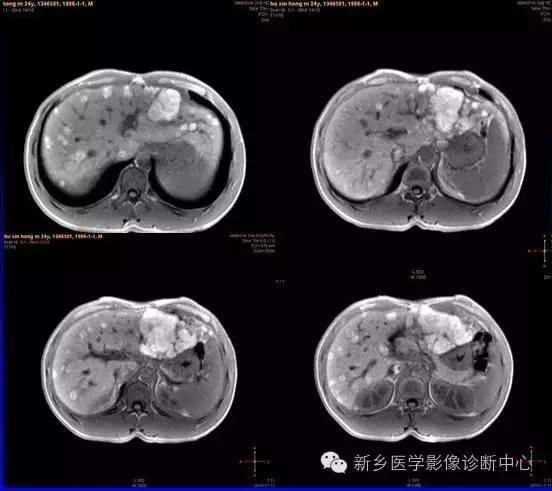

肝脏黑色素瘤

原发于肝脏的恶性黑色素瘤极其罕见。肝脏原发恶性黑色素瘤临床表现及体征均无特征性,与其他肝脏占位性、 肿瘤性病变无法区分,此为该病的临床特征。

肝脏恶性黑色素瘤的超声和 CT多表现为肝脏增大,肝内单发、 多发占位病变或弥漫性、 结节性改变, 占位性病变可为实性、 囊性、 囊实性改变,但上述改变无明显特异性, 与其他肝脏恶性肿瘤无法区分。MR T1 加权呈高信号、 T2 加权呈低信号